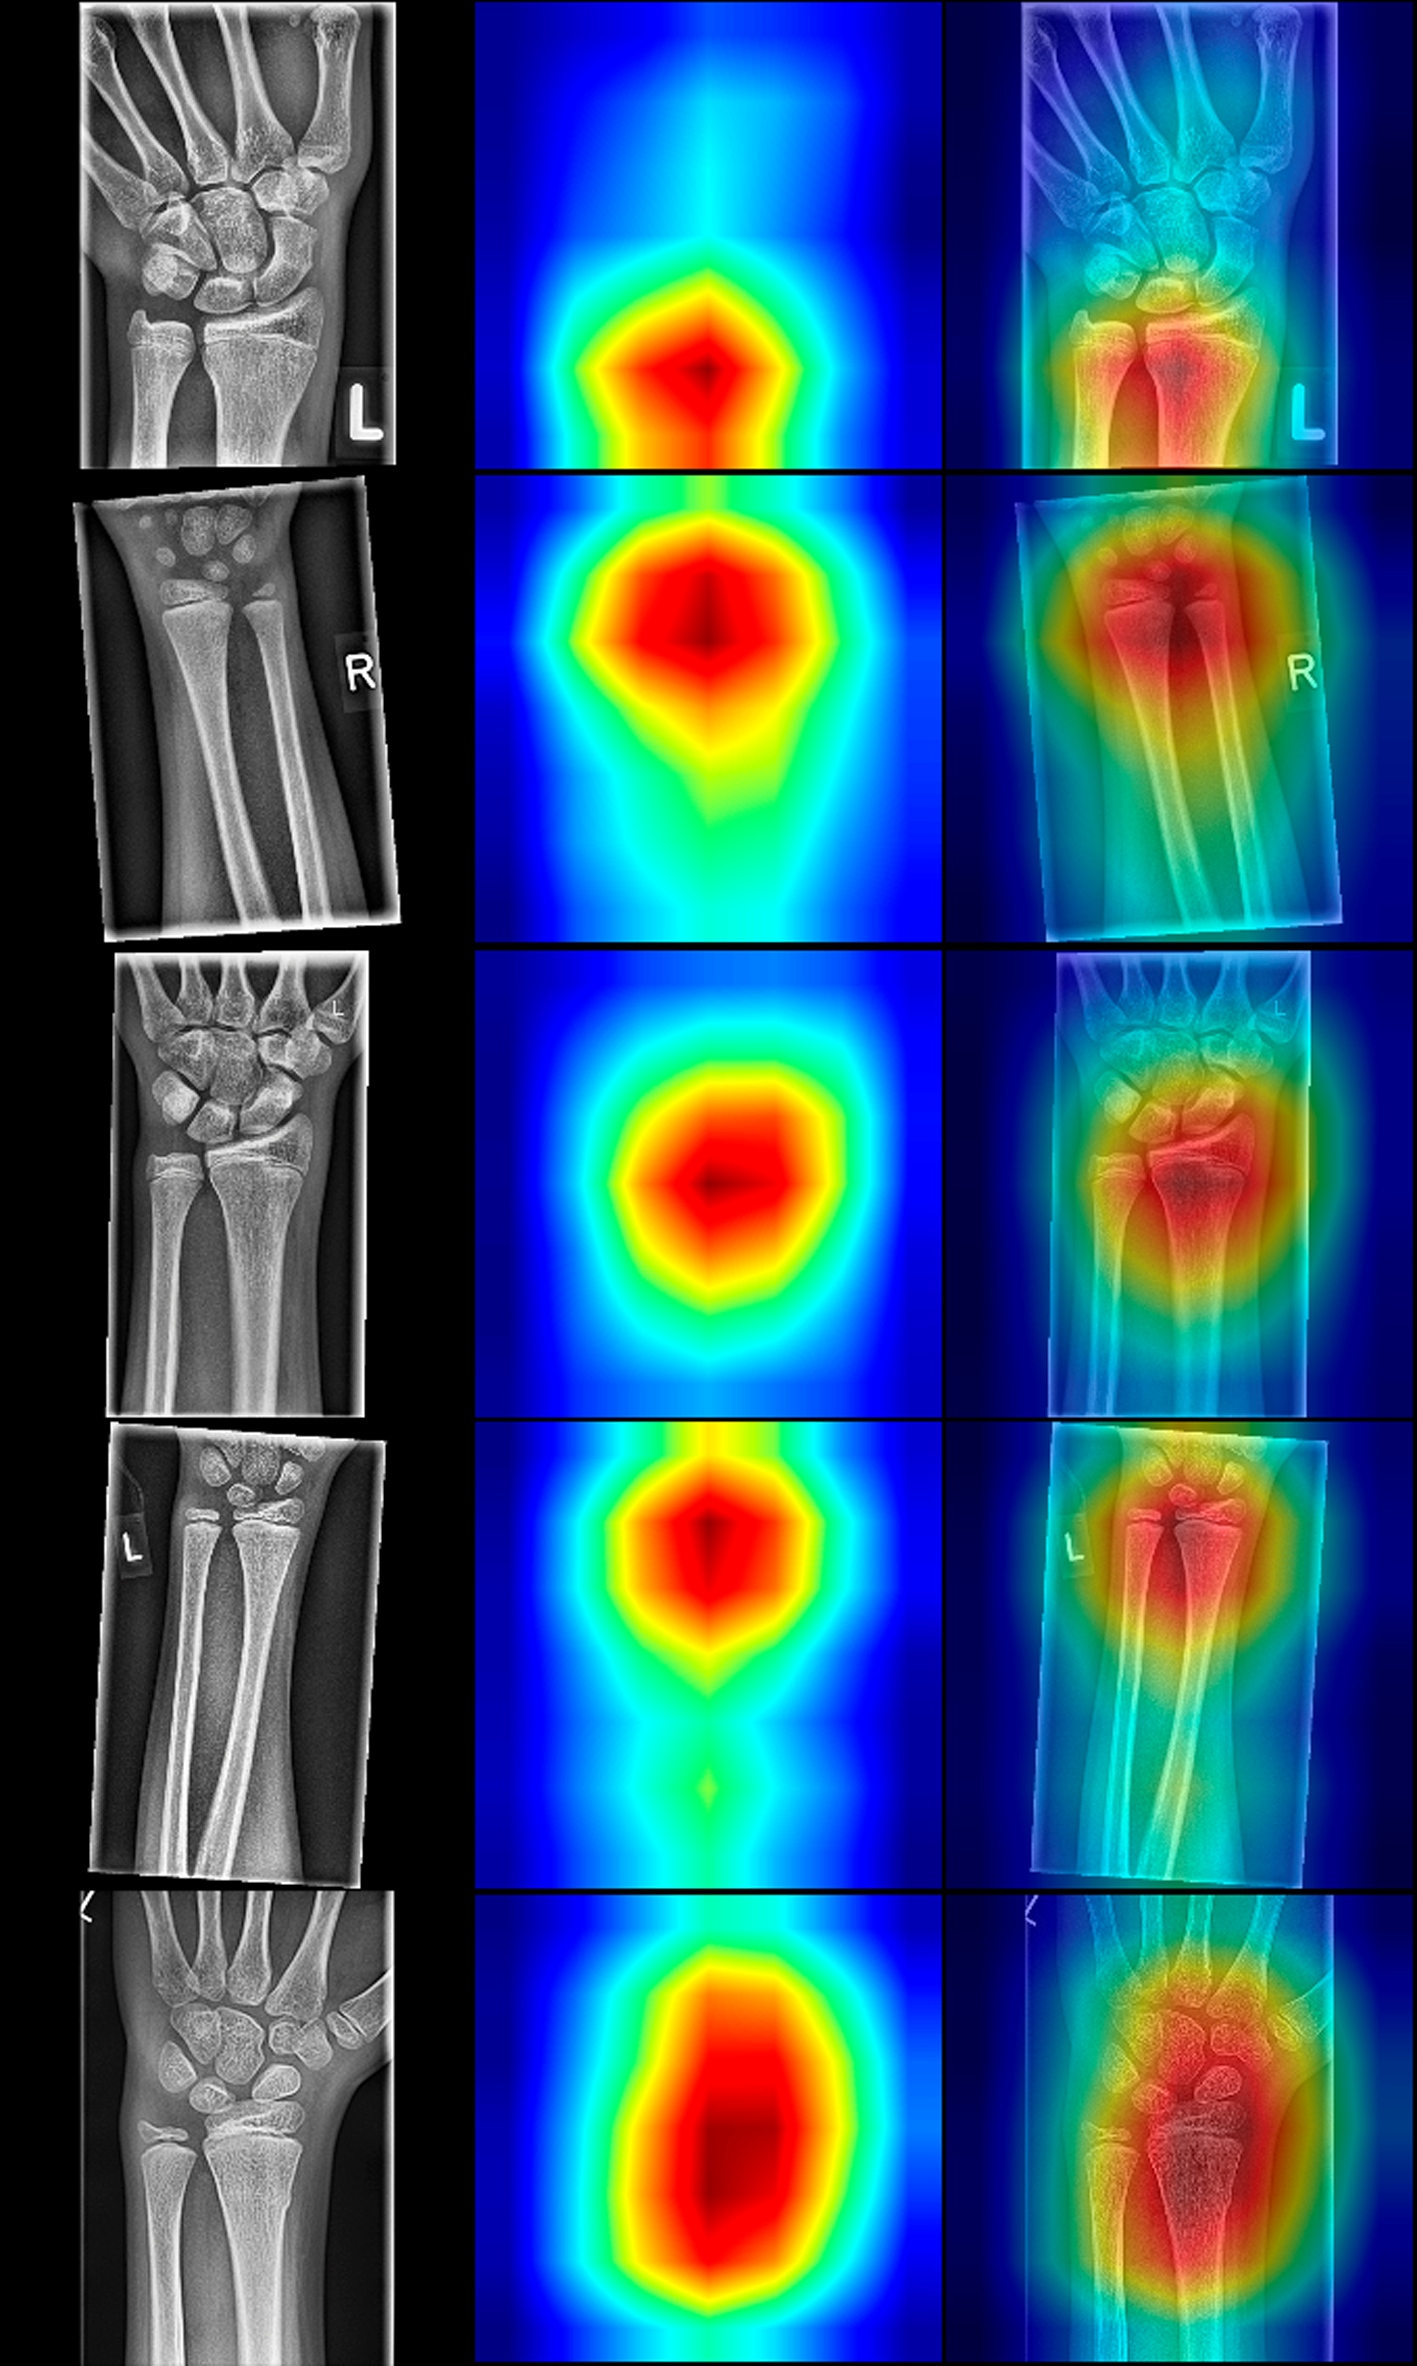

There is still an issue with AI in medicine, since CNNs are regarded black-boxes with difficulties in explaining their underlying decision-making. According to Guidotti et al. (30), a possible way to get insight into the black-box model is to explain outcomes. In classification models this means to find the most important regions of interest that contributed to the final decision. For that purpose, we have used Grad-CAM class activation maps, proposed by Selvaraju et al. (17), “highlighting” the most relevant pixels in the images. The Grad-CAM is an enhanced version of Zhou et al. (31) that can work on any CNN without modifying the CNN. The method's idea is to backpropagate the weights from the end of the model towards the last convolutional layer of the model. The backpropagated gradients represent pondering factors to the feature maps of the last convolutional layer.

Upscaled summed feature maps to the input image size result in an attention heatmap that marks the regions that contributed most towards the final outcome of the CNN. This way, we can inspect why CNN predicted a particular result and explain our models. The resulted heatmaps are presented in Figure 7 and are showing that the focus of the CNNs is on the distal forearm region, which is precisely the region where the radiologist focuses during the fracture detection. Therefore, the CNNs mimic the radiologist by sharing the same attention field during the decision-making process.

Figure 7

Random selection of radiographs positive for fracture with resNet-152 class activation maps (CAMs). The left column displays the source images, the middle column illustrates CAMs, and the right depicts fusions of source and sample images. Note that the classes are activated in the distal forearm region, even though the fields of view differ in the presented radiographs.